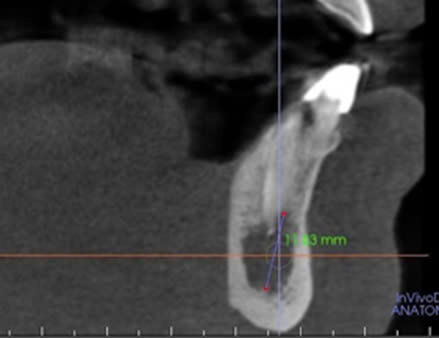

Hình 1. CBCT trước điều trị, bệnh nhân Đ.Q.Q